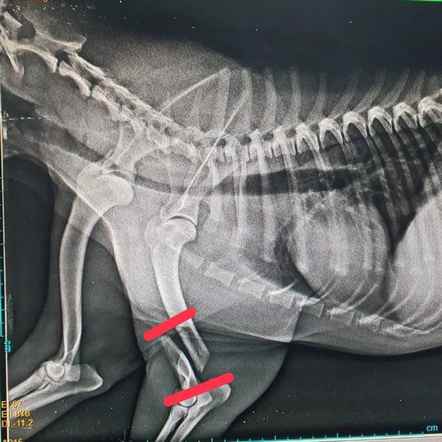

ไททัน

เพศ: เพศผู้

อายุ: 1 ปี, 7 เดือน 25 วัน

ลักษณะ: สายพันธุ์ไทย สีครีม

อาการ/โรค: ถูกรถชนขาหัก